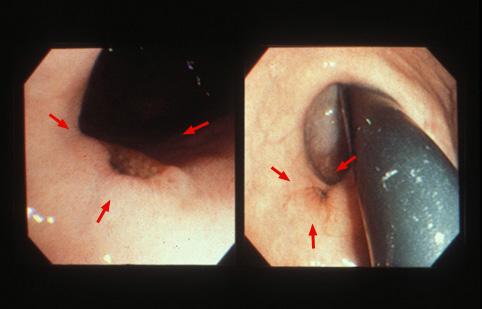

疾患(病理主体)の分類悪性上皮性腫瘍/腺癌

部位(臓器別)胃(部位)/噴門

検査方法内視鏡

腫瘍の肉眼分類0型(表在型)/IIc型(IIc)

病変の最大径(ミリ)10〜14

腫瘍の深達度m